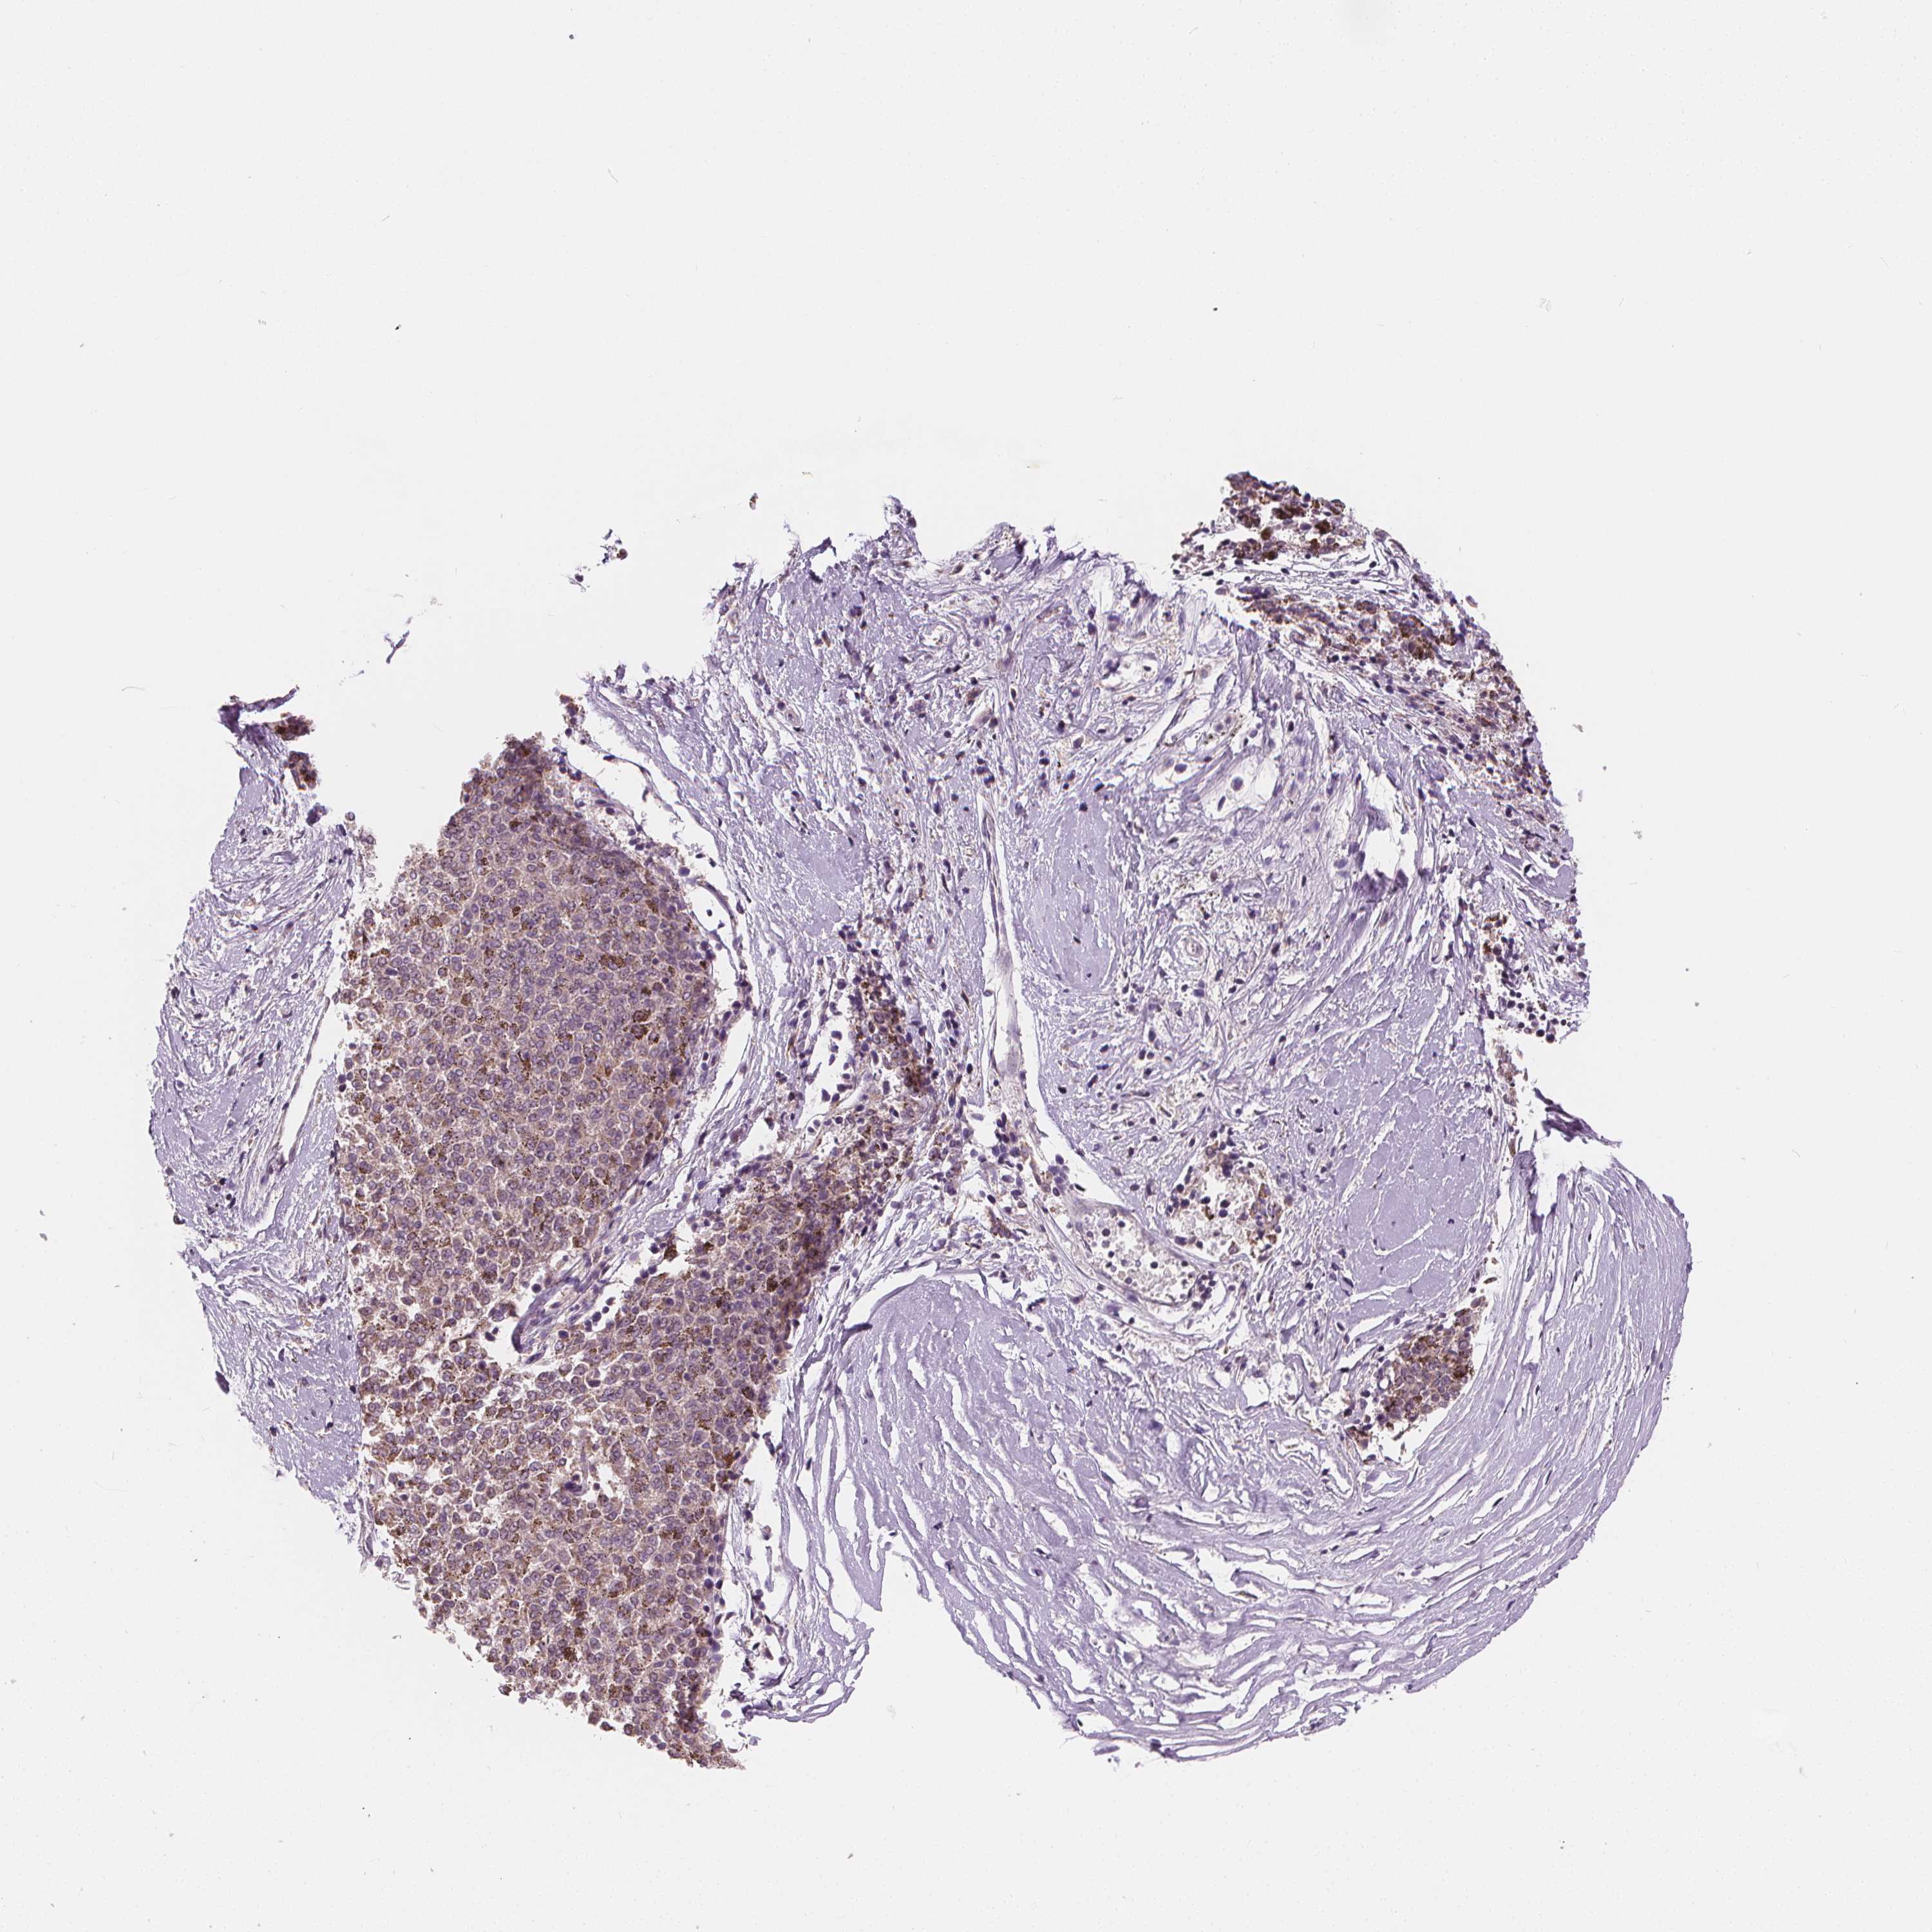

MELANOMA - Protein expressioni

A mouse-over function shows sample information and annotation data. Click on an image to view it in a full screen mode. Samples can be filtered based on level of antibody staining by selecting one or several of the following categories: high, medium, low and not detected. The assay and annotation is described here.

Note that samples used for immunohistochemistry by the Human Protein Atlas do not correspond to samples in the TCGA dataset.

Antibody stainingi

Antibody staining in the annotated cell types in the current human tissue is reported as not detected, low, medium, or high, based on conventional immunohistochemistry profiling in selected tissues. This score is based on the combination of the staining intensity and fraction of stained cells.

Each image is clickable and will lead to virtual microscopy that enables deeper exploration of all samples and also displays staining intensity scores, fraction scores and subcellular localization as well as patient and tissue information for each sample.

Antibody HPA068647

Staining

High

Medium

Low

Not detected

Intensity

Strong

Moderate

Weak

Negative

Quantity

>75%

75%-25%

<25%

None

Location

Nuclear

Cytoplasmic/membranous

Cytoplasmic/membranous,nuclear

Malignant melanoma, NOS

Malignant melanoma, Metastatic site